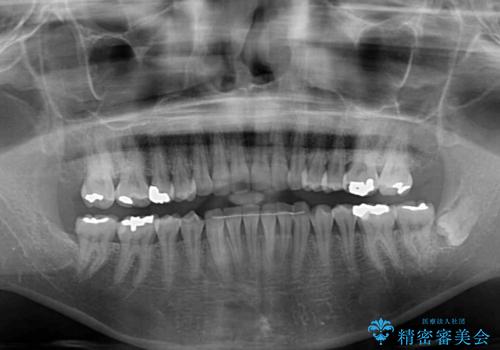

- 上下前歯のデコボコ改善をインビザラインにて行いたいとのことで来院された患者様です。

インビザラインをご希望のことで、IPR(歯と歯の間を削る)などによりスペースを獲得して、排列していくこととしました。

骨格的に上下顎が左右にずれていたため、正中位置は現状を維持したまま歯列不正を解消していくことになります。

なかなか装着時間が守れず、後戻りを繰り返しながら治療を進めたため、インビザライン治療期間期限ギリギリの5年弱の期間を要しました。